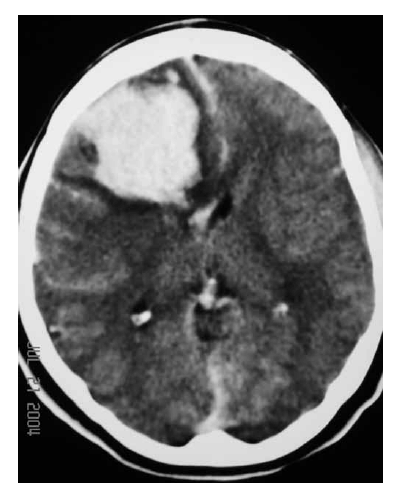

Uma mulher de 29 anos de idade teve sua gestação interrompida com 35 semanas, mediante parto cesariano, por ter apresentado quadro compatível com a doença hipertensiva específica da gravidez. No quinto dia de pós-operatório, apresentou importante dor de cabeça seguida de crises convulsivas; na avaliação laboratorial, foram atestadas plaquetopenia e alteração da função hepática. Ela foi levada à unidade de terapia intensiva, onde o plantonista observou hemiparesia esquerda e solicitou uma tomografia de crânio sem contraste, que é reproduzida abaixo.

Com base nessas informações, julgue os itens que se seguem.